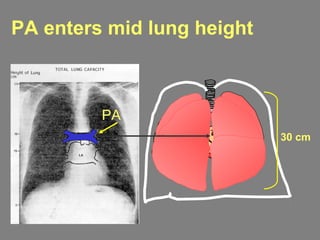

PA enters mid lung height

30 cm

PA

Gravity determines highest bloodflow at lung base 0 cm End expiration +10 cm -10 cm Ppa Pla (cmH2O) 10 5 20 10 30 20 Palv = 0